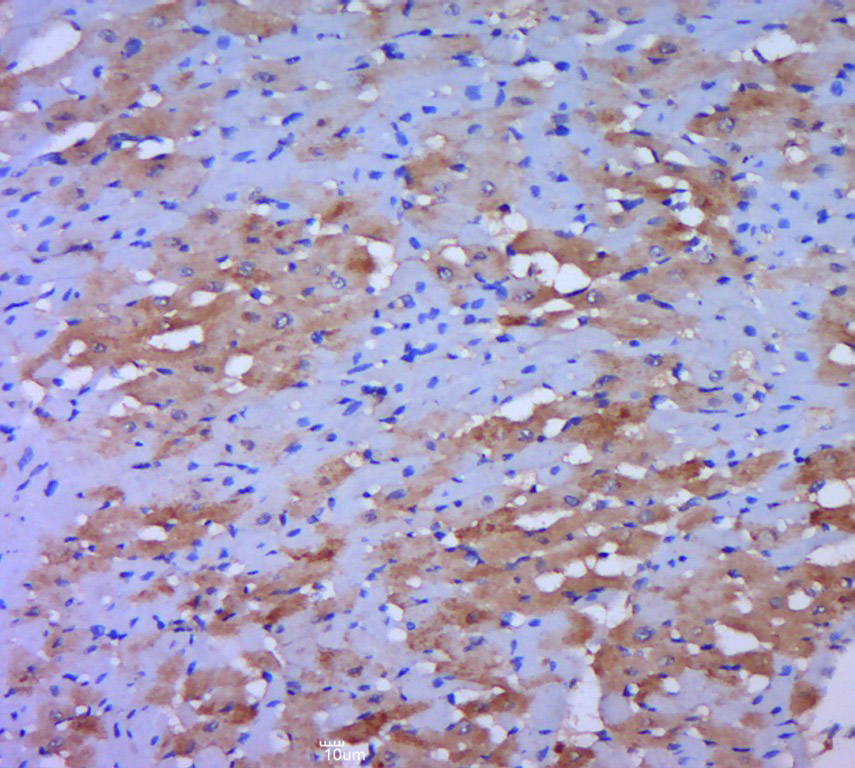

Paraformaldehyde-fixed, paraffin embedded (rat heart tissue); Antigen retrieval by boiling in sodium citrate buffer (pH6.0) for 15min; Block endogenous peroxidase by 3% hydrogen peroxide for 20 minutes; Blocking buffer (normal goat serum) at 37°C for 30min; Antibody incubation with (DLDD) Polyclonal Antibody, Unconjugated (bs-18295R) at 1:400 overnight at 4°C, followed by a conjugated secondary (sp-0023) for 20 minutes and DAB staining.